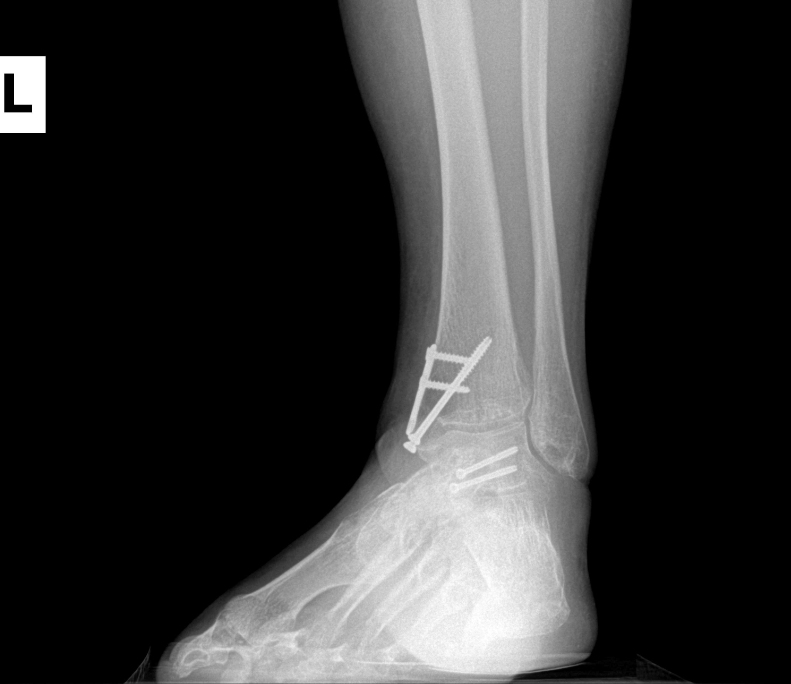

Ankle fracture repair

AF1

AF2